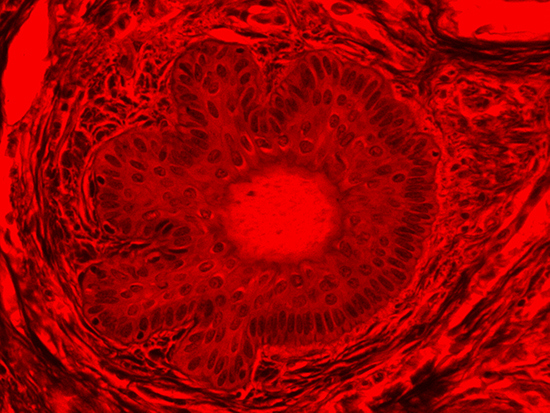

Figure 4: Brightfield Image of Dermal Tissue filtered with Red

When comparing Figure 3 with Figure 4, there is once again a significant visual difference. The most obvious feature is the change in color from green to red due to a different hardcoated filter being positioned in the optical path. The less obvious difference is the varying contrast levels caused by the filters at specific regions of the dermal tissue. For example, Figure 3 exhibits a distinct ring at the central region of the cell with additional matter within. In Figure 4, the ring is extremely faint and the internal matter is not visible. With that said, the cell and surrounding dense materials are more evident in Figure 3, whereas the muscle fibers and collagen are more pronounced in Figure 4.